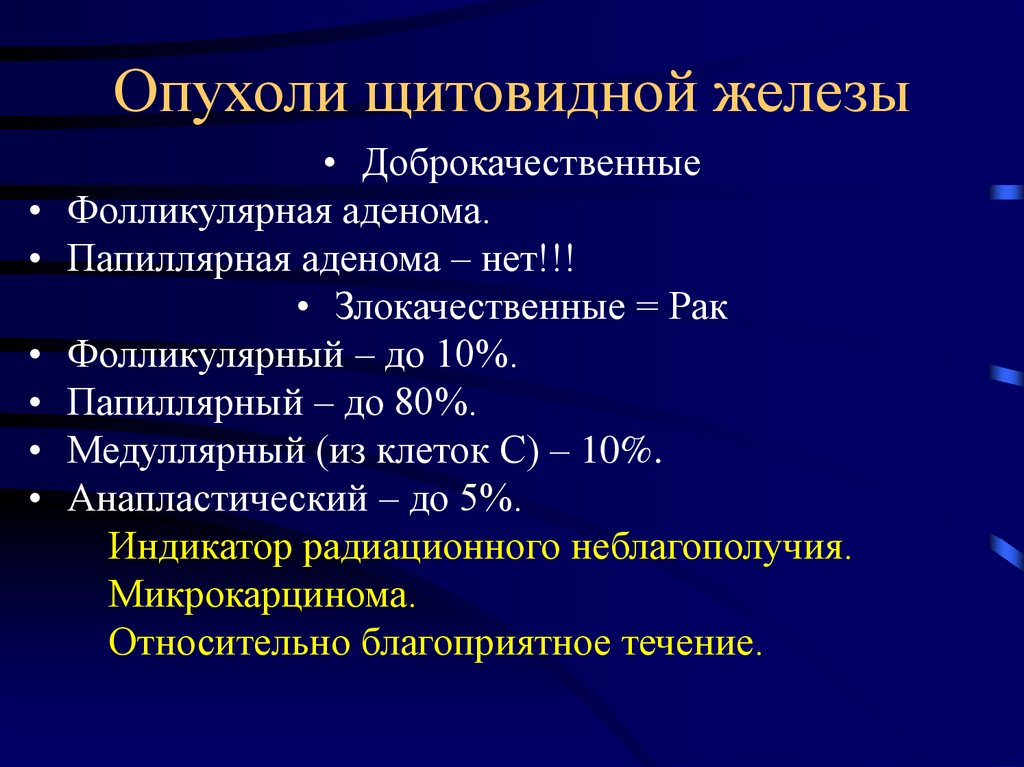

Амебиазный абсцесс печени. Солитарный абсцесс печени. Амебный абсцесс печени кт. Злокачественные опухоли щитовидной железы классификация. К злокачественным новообразованиям щитовидной железы относятся:. Доброкачественные щитовидной железы классификация. Доброкачественные новообразования щитовидной железы.

Злокачественные опухоли щитовидной железы классификация. К злокачественным новообразованиям щитовидной железы относятся:. Доброкачественные щитовидной железы классификация. Доброкачественные новообразования щитовидной железы. Классификация заболеваний щитовидной железы. Классификация хирургических заболеваний щитовидной железы. Заболевания щитовидной железы классификация этиология. 1. Классификация заболеваний щитовидной железы?.

Классификация заболеваний щитовидной железы. Классификация хирургических заболеваний щитовидной железы. Заболевания щитовидной железы классификация этиология. 1. Классификация заболеваний щитовидной железы?. Опухоль печени доброкачественная кт. Первичные злокачественные опухоли печени. Злокачественные новообразования печени кт. Первичные и Метастатические опухоли печени.